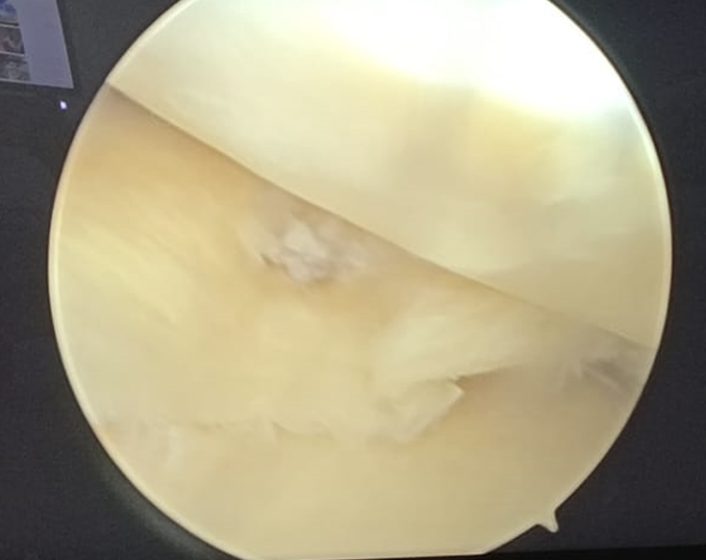

Torn Medial Meniscus inside Knee Joint